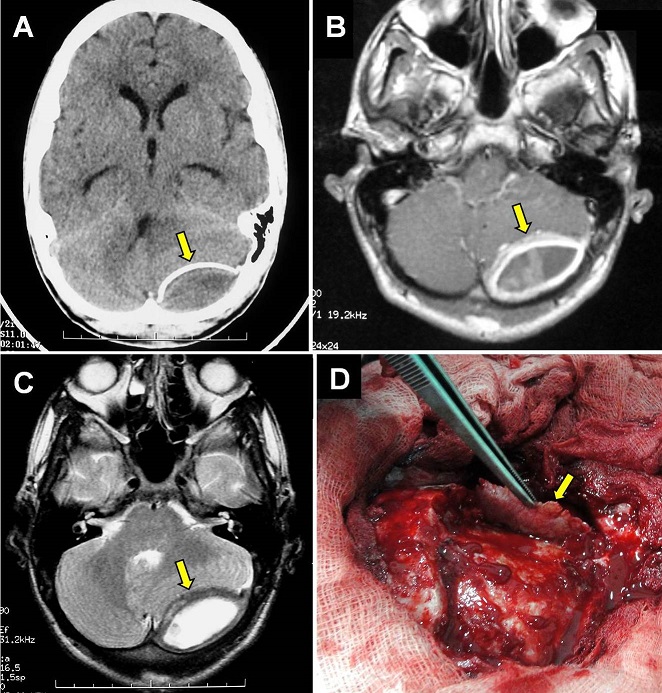

A 15-year-old adolescent presented to us with mild headache, progressive dizziness and recent vomiting since 2 weeks without seizures. There was a history of head injury (neglected) following a stone-throwing incident 2 months earlier. On examination, he was conscious with a left cerebellar syndrome but without other neurologic deficit. Routine biologic data were normal. CT-scan revealed left posterior fossa extradural lesion with hypodensity in the center and calcified wall (A). MRI showed that the lesion was liquid with homogeneous ring enhancement following gadolinium injection and cerebellar compression (B and C). A sub-occipital craniotomy was done and a chronic liquefied hematoma was removed. There was a thick hard calcified wall relatively adherent to the duramater (D). Postoperative period was uneventful and the patient was discharged symptoms free. Histologically, the wall contains large areas of ossification. Ossified chronic epidural hematoma is a very rare complication following head injury. The blood accumulates slowly from a venous source becomes chronic extradural hematoma and becomes calcified or ossified due to an inflammatory reaction of the dura especially in children. This rare phenomenon should be considered in the differential diagnosis of other traumatic epidural and subdural hematomas.